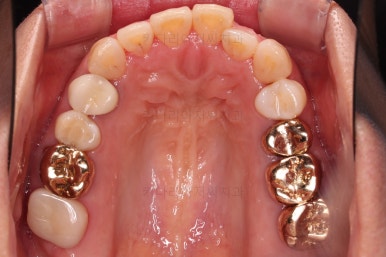

초진 시 입안의 모습입니다.

아랫니 큰 어금니 하나가 없어서 임플란트를 원하셨던 환자분이셨어요.

앞니가 조금 삐뚤고, 아랫니는 사이사이에 틈새가 있었지만 전체적인 교정은 원치 않으셨어요.